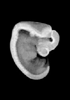

Carnegie Stage 16 (37 post-ovulatory days)

Most embryos at stage 16 are approximately 37 postovulatory days old and measure 11-14 mm in length. Distinguishing criteria for this stage include the external appearance of retinal pigment, the nasal pits face ventrally, pharyngeal arch 2 is more massive and conspicuous than arch 3, auricular bumps begin to appear, and the thigh, leg, and foot can be distinguished in the lower limb.